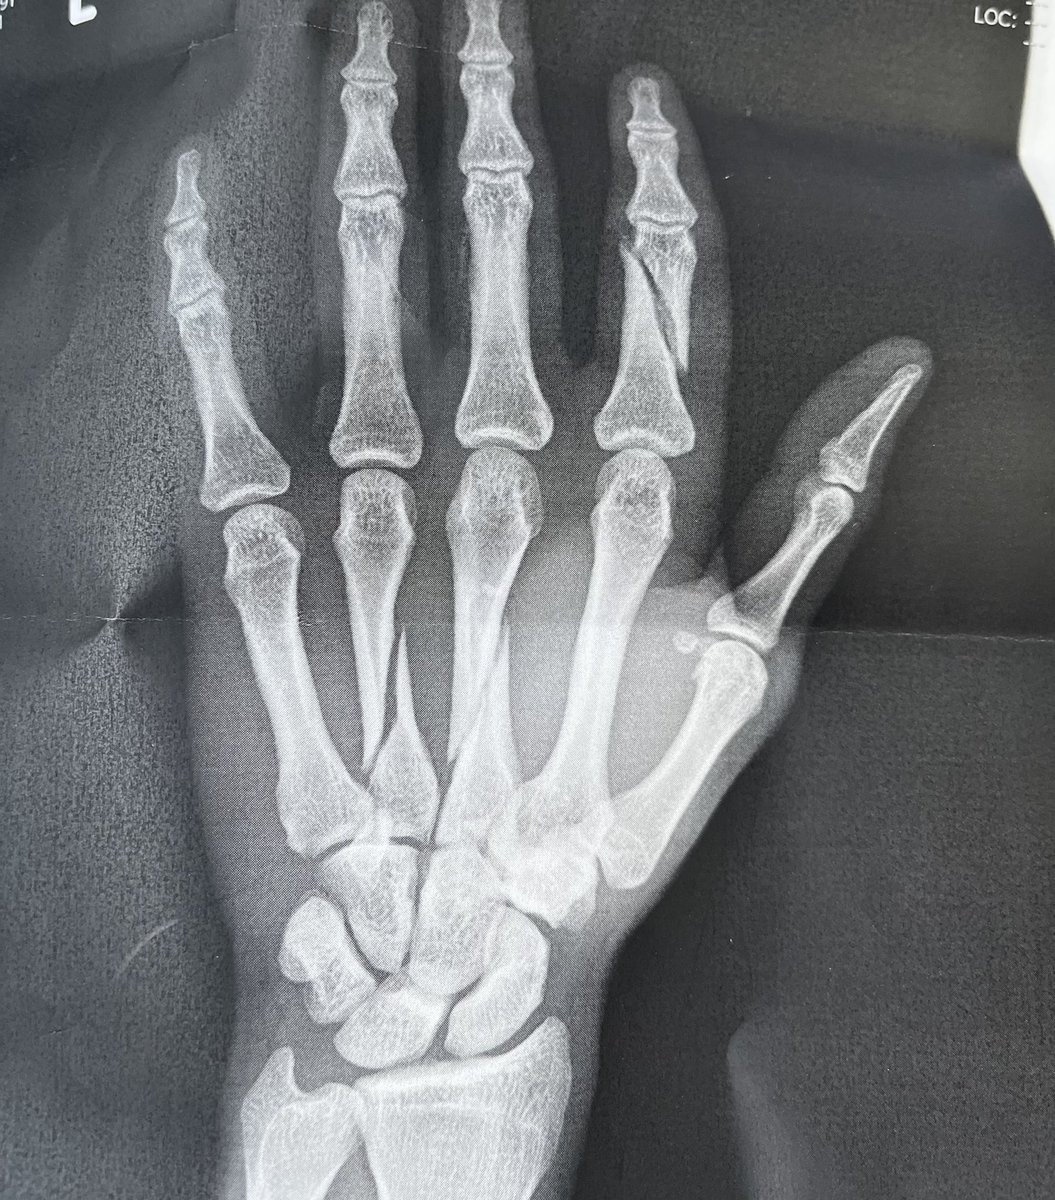

ボルト3本×3本×2本 入れました! 少し疲れました! 皆さんたくさんのメッセージ ありがとうございました😭

皆さんたくさんのコメント 本当にありがとうございます。 左第二基節骨 第三第四中手骨骨折でした この手が守ってくれなかったらもっと大きな怪我になっていたかもしれないので守ってくれた左手に感謝です。 今の現状です。 写真不快に思われた方はすみません。 復帰に向けて一歩一歩頑張ります。 twitter.com/maru4686/statu…